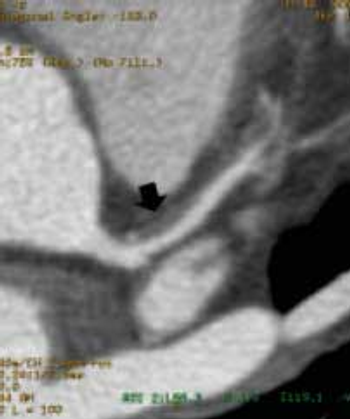

In a before-and-after study with CT imaging, signs of large vessel vasculitis and aortic wall thickening improved for some but not all patients treated with steroids for giant-cell arteritis